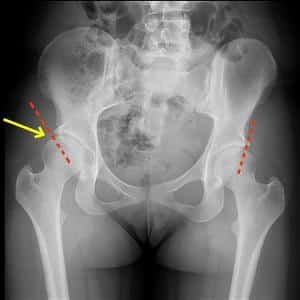

Интерпретацию результатов ультразвукового исследования проводит врач-ортопед. При анализе УЗИ тазобедренных суставов оцениваются углы положения бедренной кости относительно вертлужной впадины – угол α и угол β.

Угол альфа формируется при проведении линии, параллельной латеральной стенке подвздошной кости, и отражает степень развития купола вертлужной впадины. При нормальном строении сустава угол составляет около 60⁰. Угол бета определяется между основной линией и линией хрящевой крыши и равен 55˚. Для детей разработана специальная таблица нормальных значений углов тазобедренных суставов при дисплазии.

Следует отметить, что некоторые отклонения от нормы возможны, но они считаются аномальными. Патологическими признаками являются альфа-углы, находящиеся в диапазоне 39-40°. Это может указывать на наличие подвывиха сустава или дисплазии. В таких случаях бета-углы превышают 77°.

Суставы у взрослых характеризуются высокой эхогенностью вертлужной губы и волокнистой структурой связок. Синовиальная оболочка может не визуализироваться. Расстояние от шейки бедра до суставной капсулы составляет 0,6-0,9 см.

В зависимости от величины углов альфа и бета, а также других показателей, суставы классифицируются на четыре типа:

- Тип I: угол альфа ≥60˚. Что означает тип сустава 1а? Этот код указывает на нормальное развитие ребенка, головка бедра в покое и при нагрузке – центрирована, хрящевой выступ широкий и хорошо покрывает головку.

- Тип II: угол альфа находится в диапазоне 43-59˚. Покрытие головки составляет 40-50%. Диагноз – физиологическая задержка оссификации. Такие результаты требуют повторного осмотра.

- Тип III: угол α менее 43˚. Костная крыша скошена и немного вогнута, покрытие головки – короткое и деформированное. В таких случаях ставится диагноз подвывих бедра. Ребенок нуждается в регулярном наблюдении с частотой один раз в месяц.

- Тип IV: угол α равен 43˚. Покрытие головки отсутствует, хрящевой выступ сжат между головкой бедра и подвздошной костью. Эти показатели указывают на вывих бедра. При неэффективности консервативного лечения может потребоваться коррекционная операция.